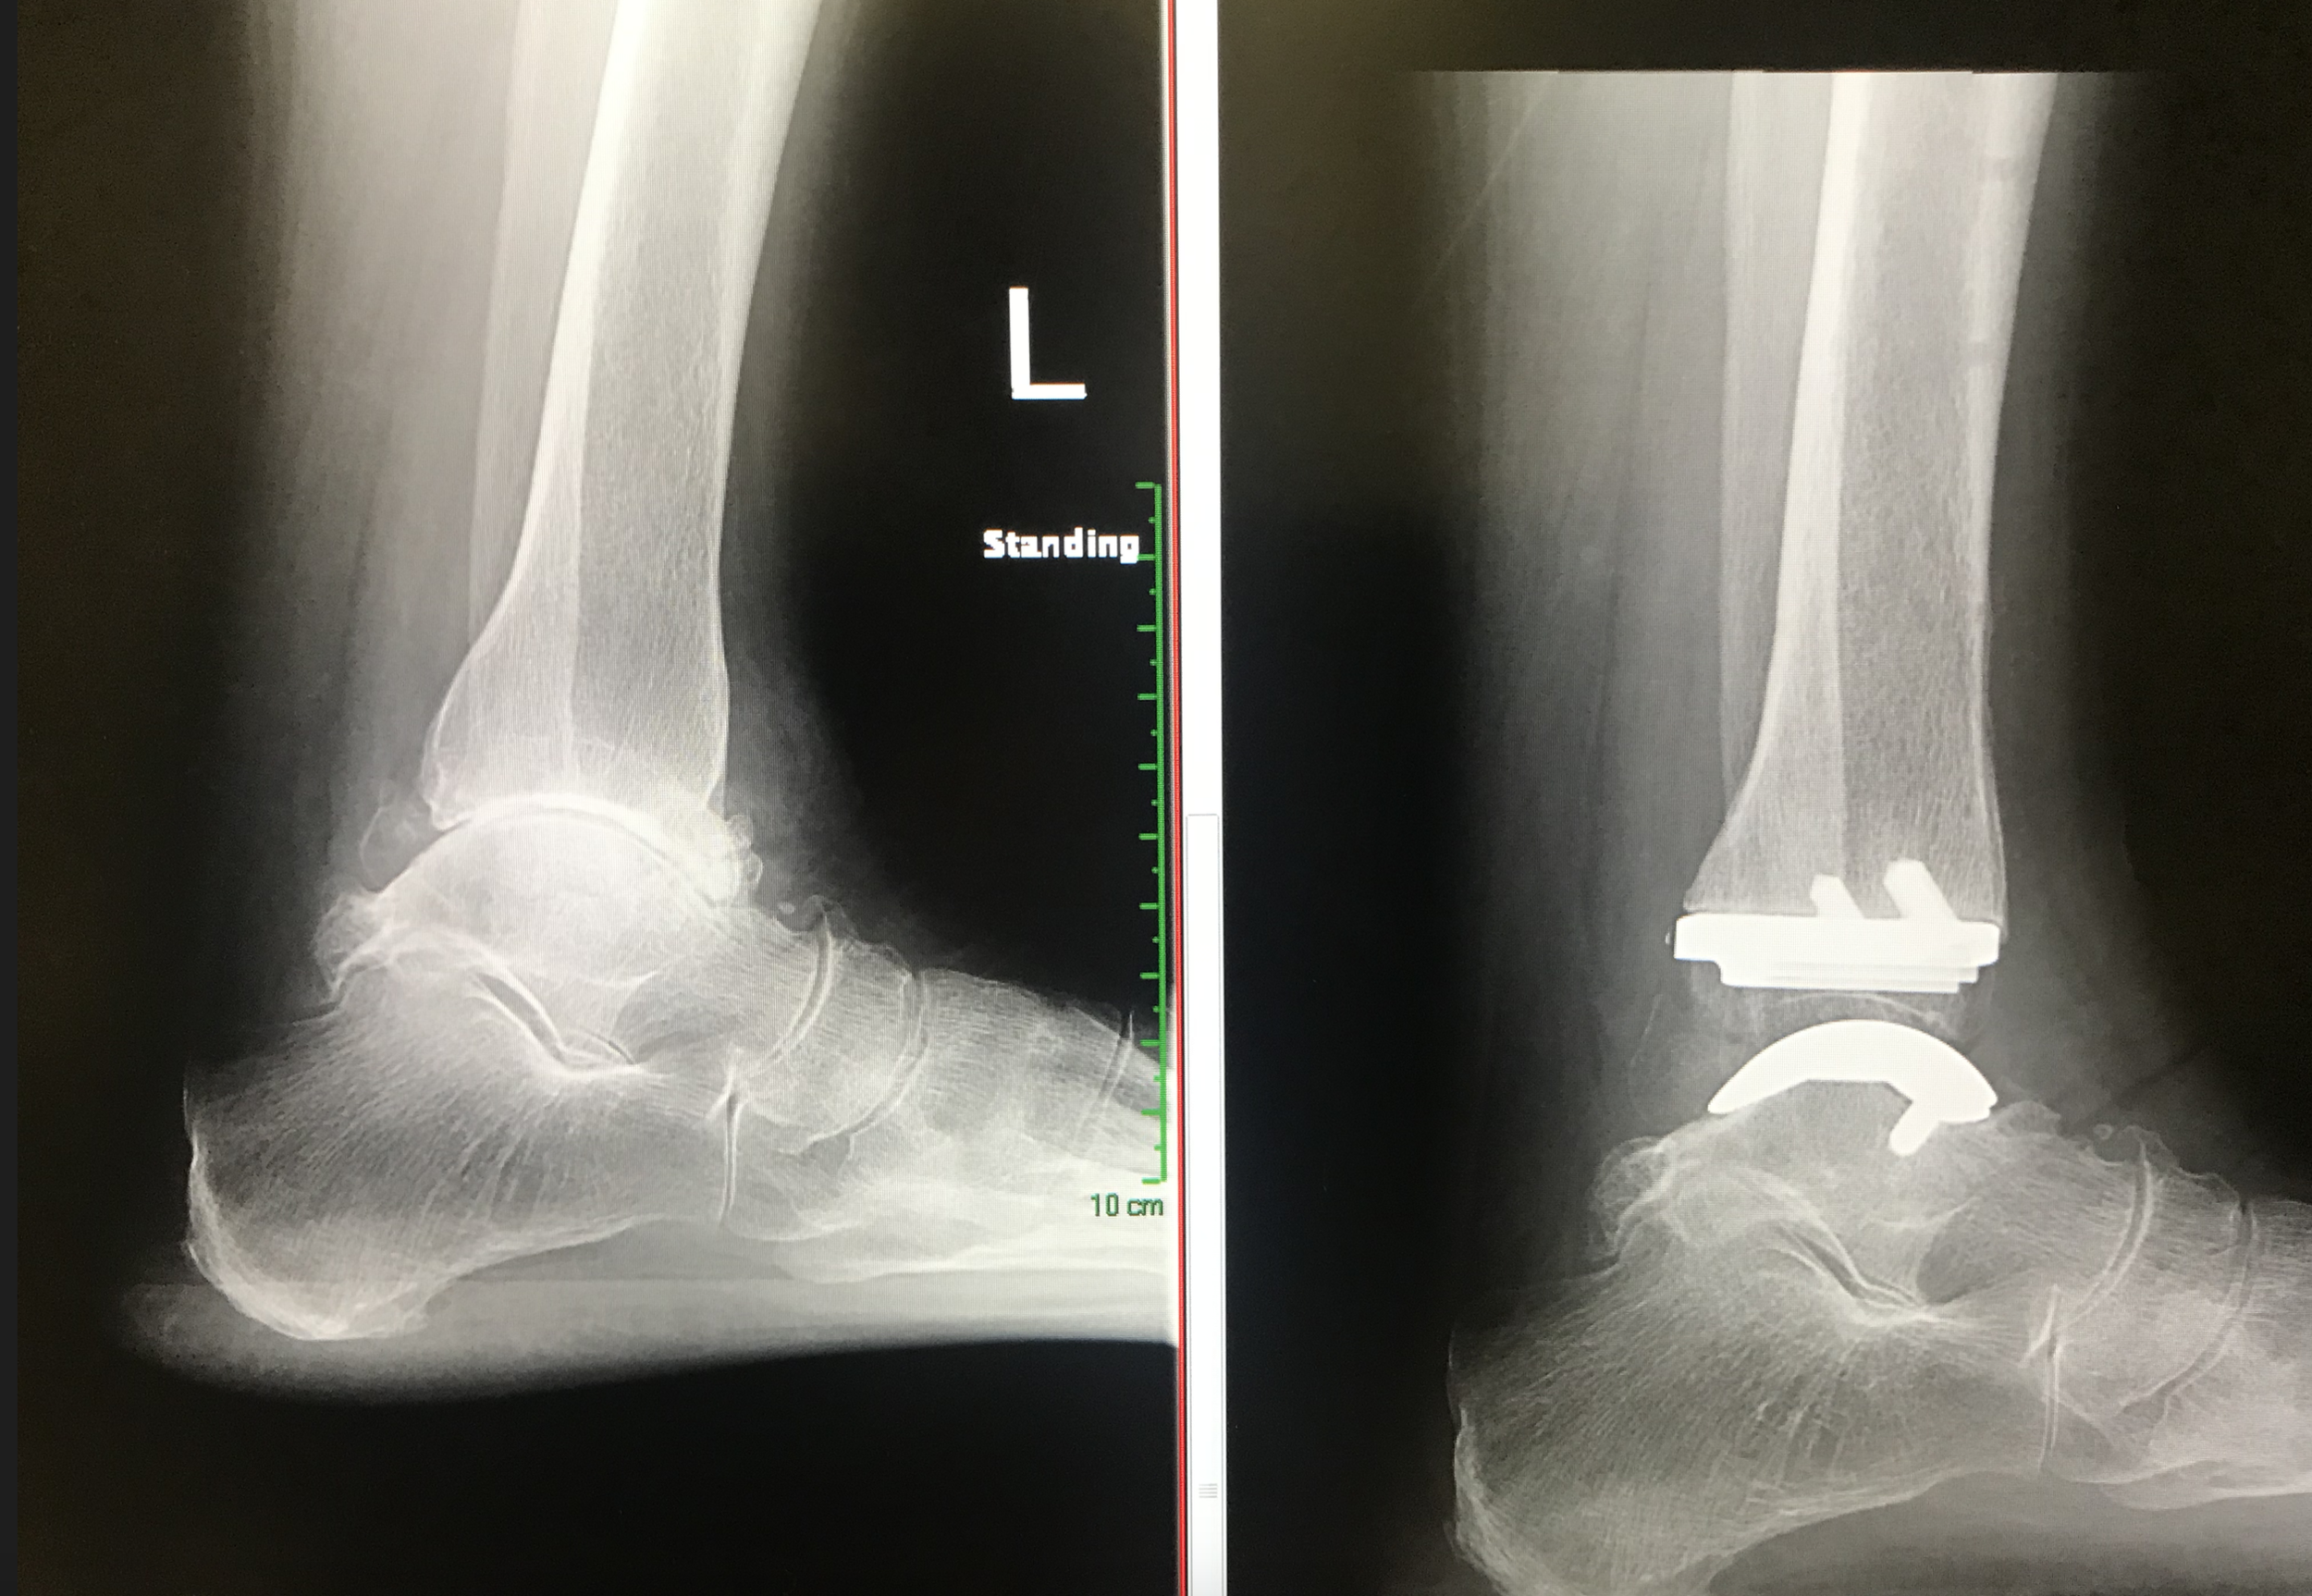

Total Ankle Replacements: Infinity Implants

This operation replaces the painful arthritic ankle joint with an artificial metal and polyethylene joint.

Infinity Total Ankle Replacement

This implant is made by Wright Medical USA and involves replacing the bony surfaces on both sides of the joint with metal bearings. The polyethylene spacer is attached to the tibial bearing but free to articulate with the talus bearing.

Infinity ankle replacement shown in a model skeleton. The implants replace both tibia and talus articular surfaces and have a high density polyethylene articulating spacer between the two metal surfaces.